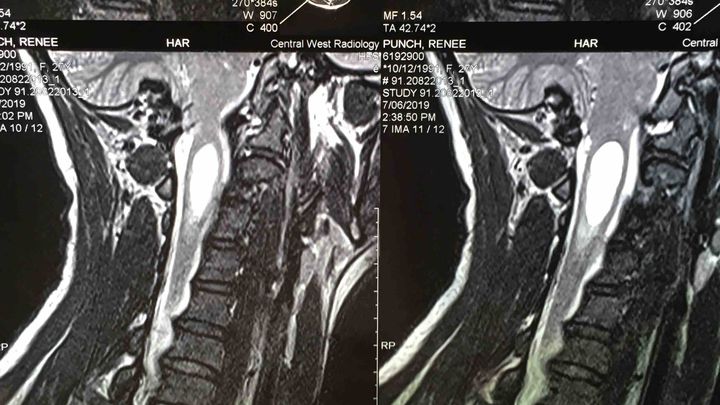

My partner Renee is being rushed in for emergency surgery in Sydney. She is having Suboccipital Craniectomy and a Patch Graft for her Chiari Malformation and Syrinx decompression. We have recently found out that it has grown rather rapidly which can cause quadriplegia if she doesn’t have the surgery done. Unfortunately as it is in such a short time period we don’t have the money to pay for the surgery and we need your help. The specialists themselves is going to cost $6000, then we have the MRI which is another $800 and also the anaesthetists will apparently have additional fees which we have been told are $3150 and only 30% is covered by health care.